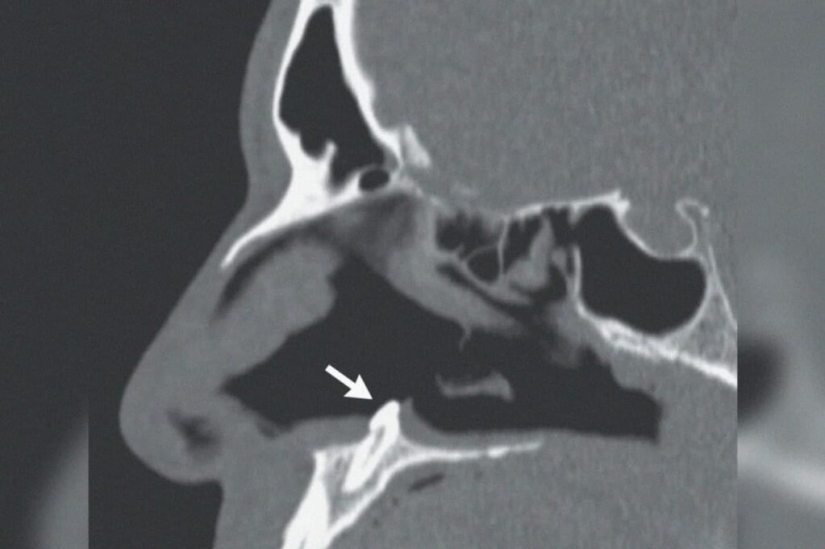

Por Pictolic https://www.pictolic.com/es/article/en-los-eeuu-los-cirujanos-extirparon-un-diente-que-creci-en-la-nariz-de-un-hombre.htmlA veces el cuerpo humano arroja sorpresas a los médicos, obligándolos a romperse la cabeza a fondo. Los cirujanos del Complejo Médico Mount Sinai en Nueva York recientemente tuvieron que extirpar un diente de un hombre de 38 años que le había crecido justo en la nariz. No era una nimiedad, sino un colmillo real con una longitud de 14 mm!

El paciente fue a los médicos quejándose de dificultad para respirar. Según él, los problemas comenzaron hace varios años, pero ahora se han vuelto simplemente insoportables. Un examen superficial reveló una curvatura del tabique nasal en el paciente, así como un cierto sello en la profundidad del pasaje nasal.

La tomografía lo puso todo en su lugar. El llamado diente ectópico resultó ser un sello incomprensible. Este es el nombre de los dientes que han crecido en lugares inadecuados para ellos. Este fenómeno raro, pero no excepcional, puede estar asociado con el crecimiento de los dientes de leche. A veces, tal diente no se cae, sino que permanece en algún lugar de los tejidos.

También sucede que un diente ordinario erupciona en el lugar equivocado y crece donde le plazca. Curiosamente, los dientes ectópicos pueden aparecer tanto en la infancia como en la edad adulta. En el caso del paciente del Monte Sinaí, no se sabe exactamente cuándo comenzó a crecer el diente, porque mientras era pequeño, no molestó al propietario en absoluto.

Pero el Monte Sinaí no fue el caso más favorable. Por lo tanto, tuve que hacer una operación complicada para extraer un diente de mi nariz. Ahora, cuando han pasado 3 meses desde la extracción, el paciente se ha recuperado completamente, se siente muy bien y puede respirar completamente.